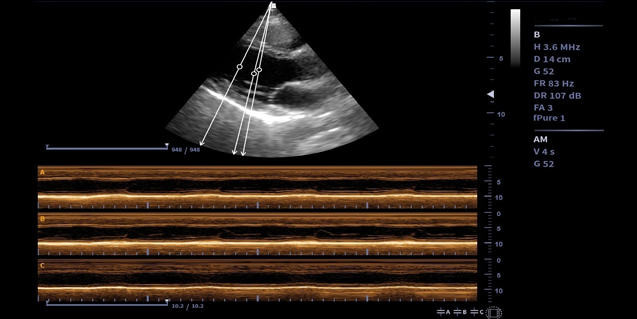

临床图像